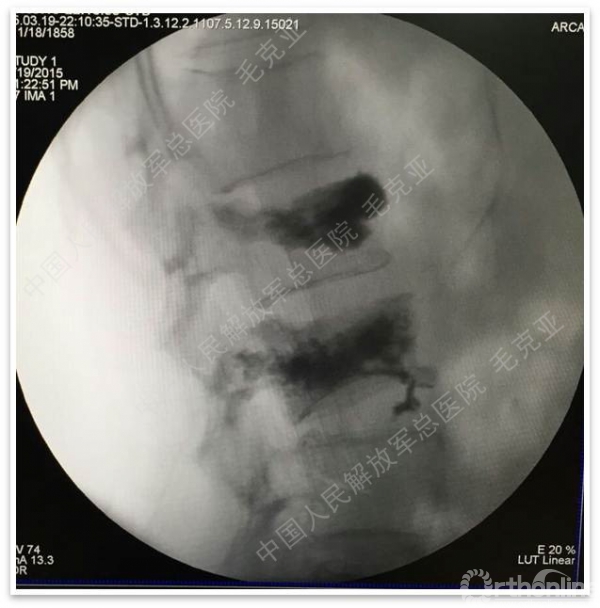

导语:随着社会老龄化的不断加速,骨质疏松性椎体压缩骨折作为一种普遍存在的老年骨科疾病已经成为现今骨科界的一个热点话题。传统的保守疗法治疗效果不佳,而现有的椎体增强技术又具有多种风险和缺陷。针对这种现状,中国人民解放军总医院毛克亚教授提供了一种新的解决方法。